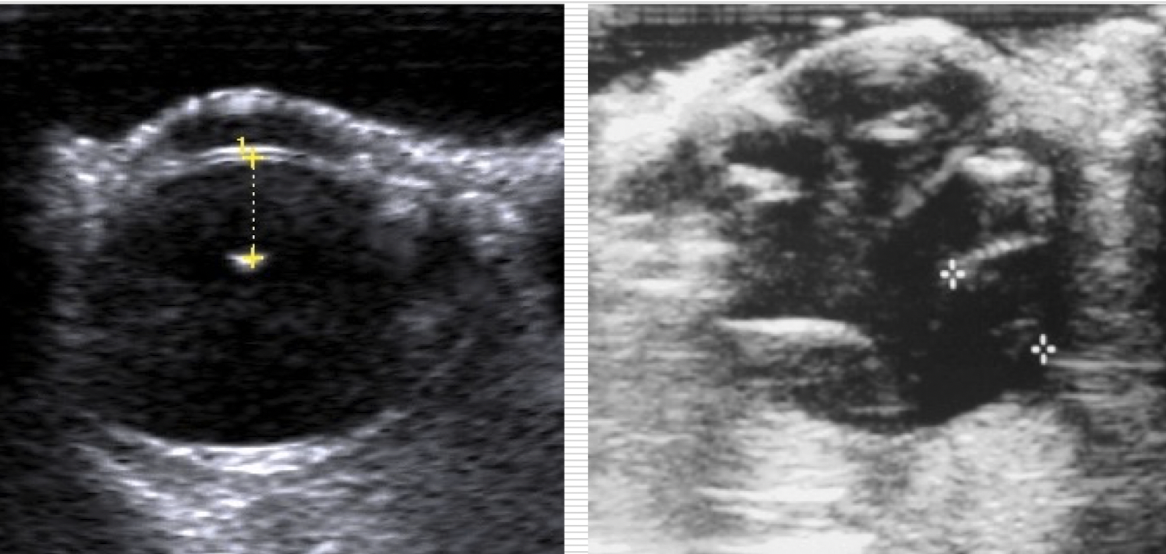

how to see into eye?

A

ultrasound

retinal detachment